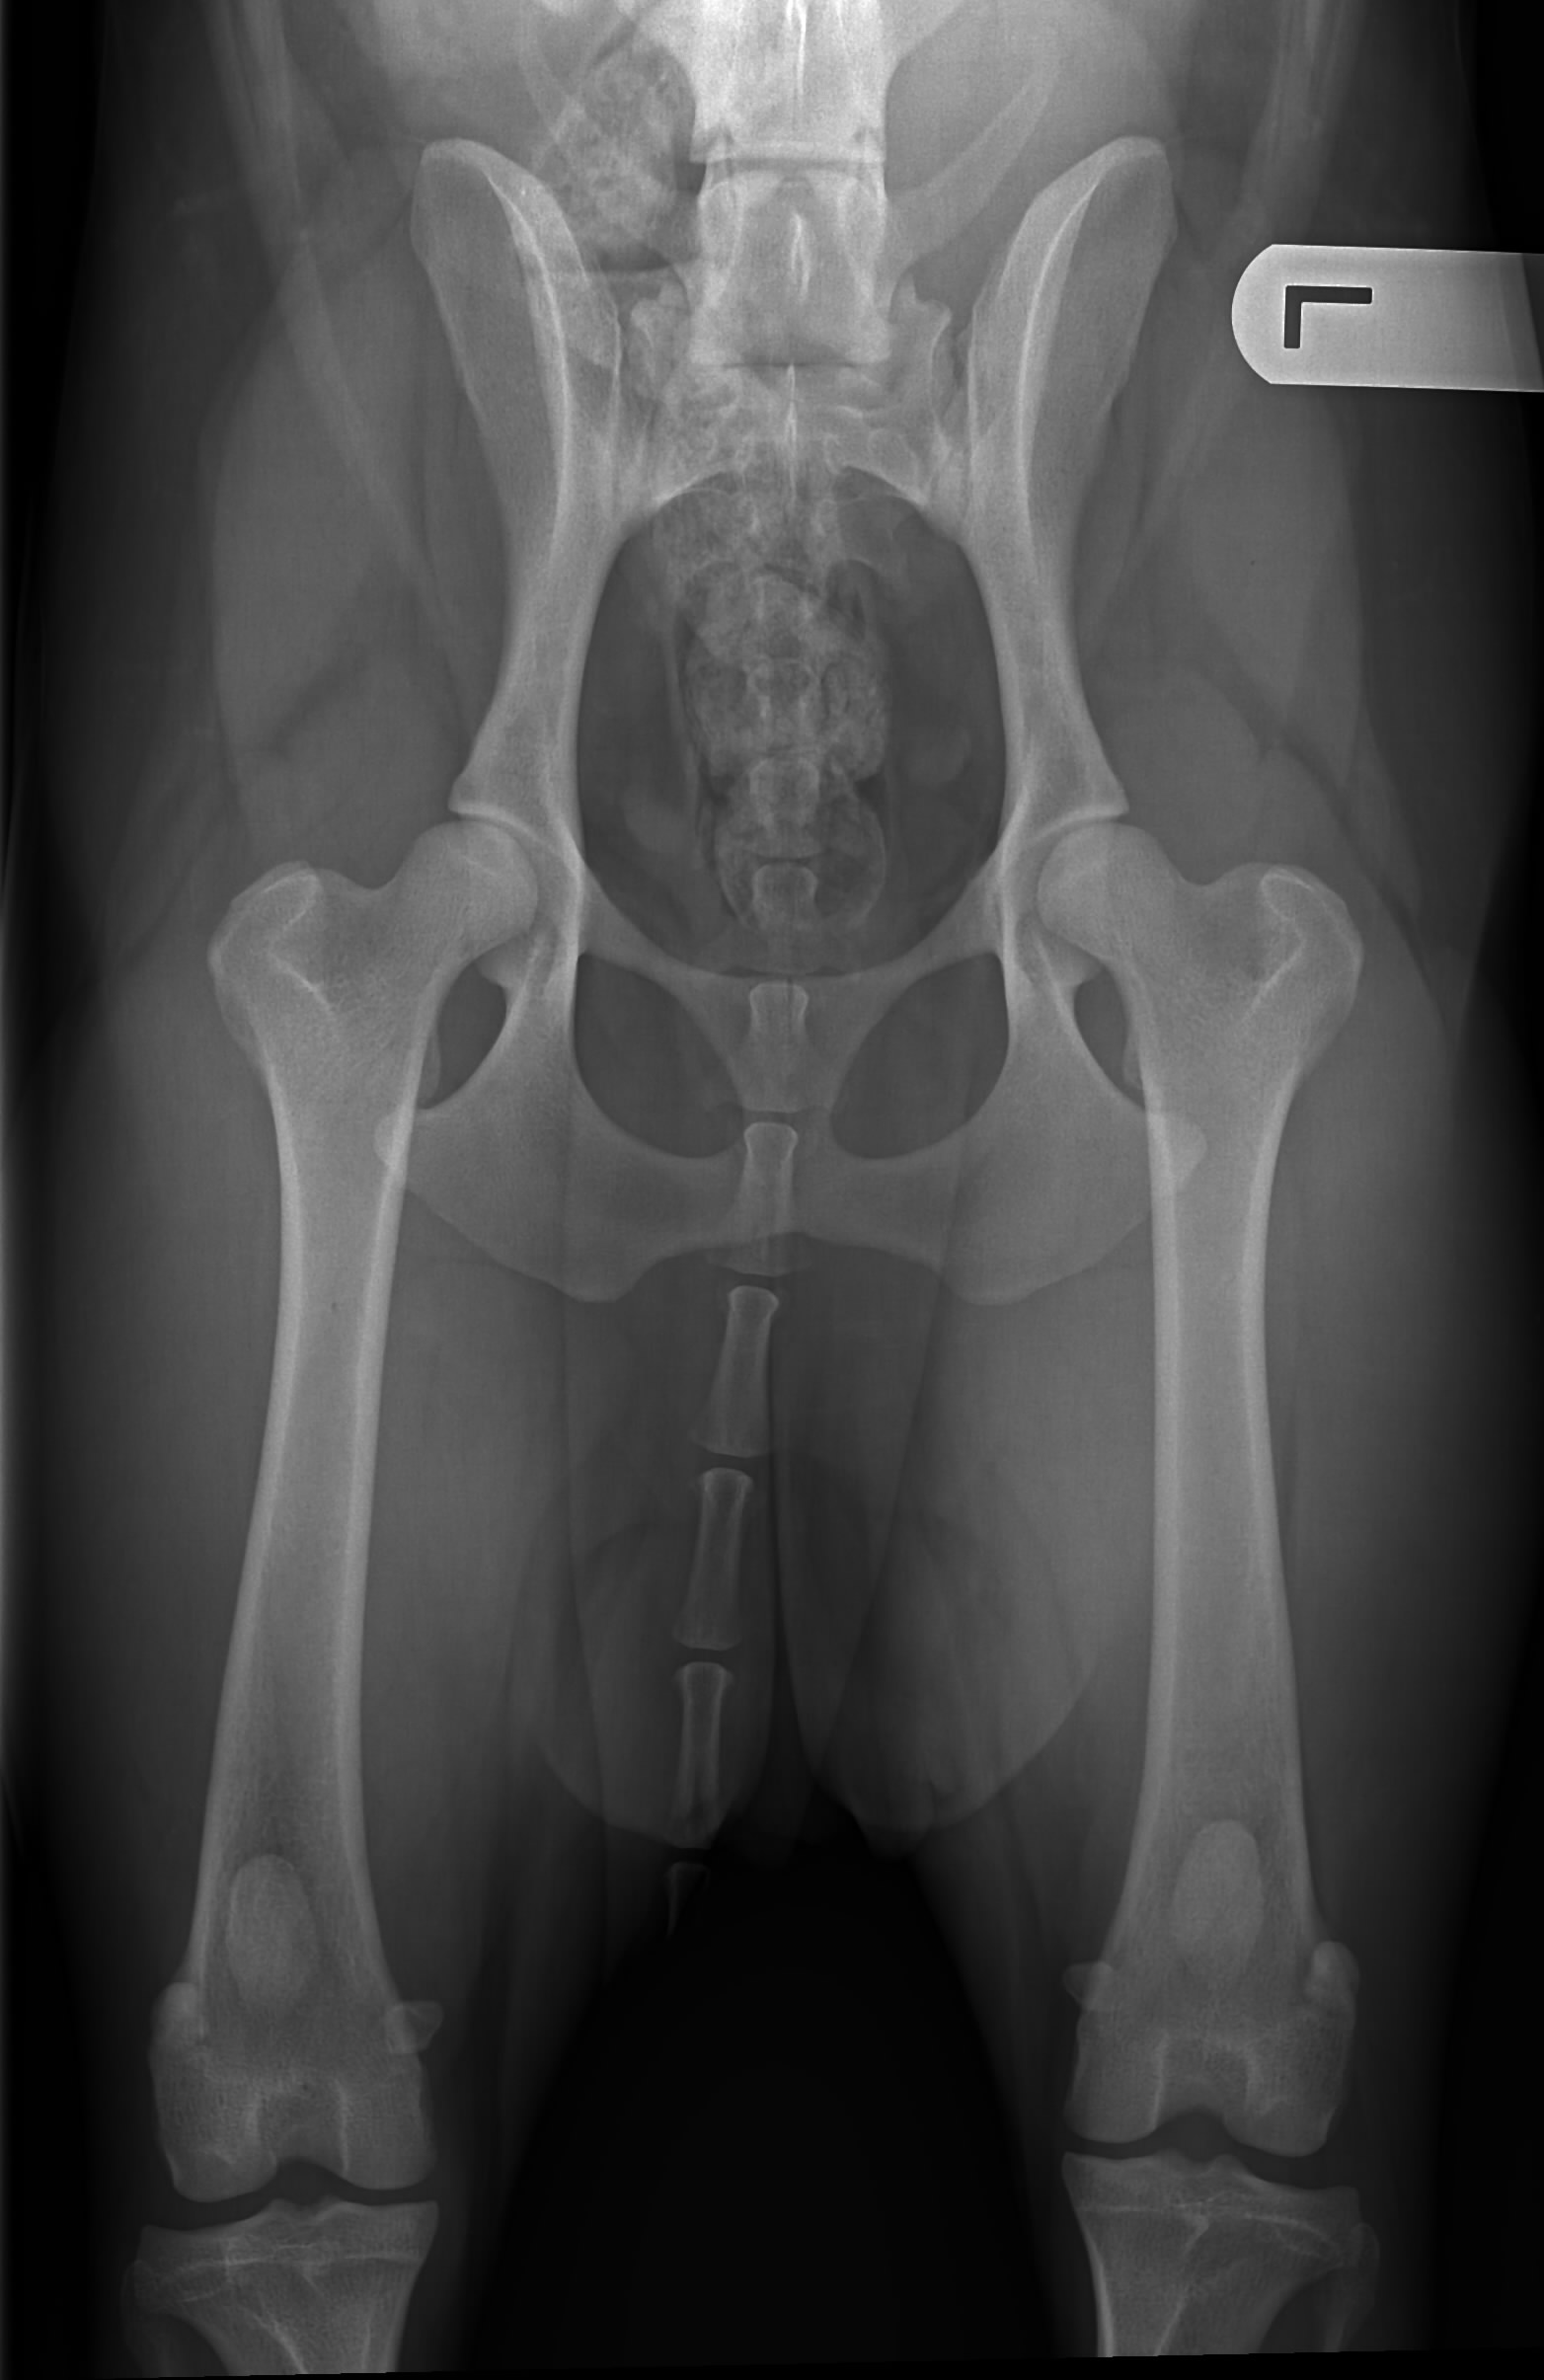

1. Officiële HD-foto

Hieronder de heupfoto en officiële uitslag. De dierenarts (Dr. Strikkers) was heel tevreden met de heupen die hij zag, voor een hond van ruim 2,5 jaar oud. De officiële uitslag is dan ook prima: HD A!

| Bewegingsapparaat | Heupdysplasie: | Officieel: HD A |